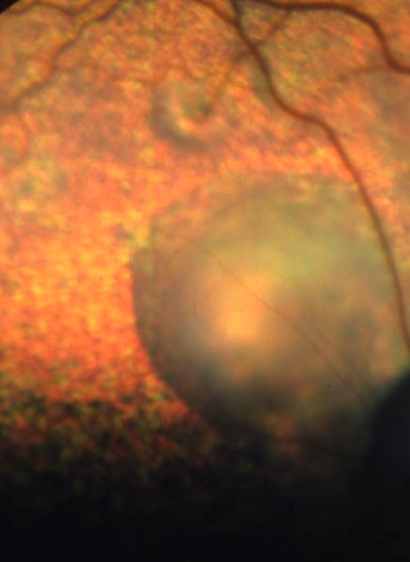

retinal hemorrhage

wrinkled →serous retinal detachement- out of focus, hyporeflective tapetum